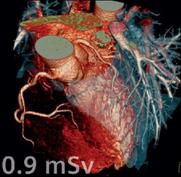

发挥了重要作用。CT的临床应用非常广泛,包括头颈部疾病、胸部疾病、心脏及大血管的CT检查、腹部疾病检查等等。在工业上可以检测高密度和大尺寸物体、多孔材料或微米级的电路元件,检测内容包含内部缺陷、杂质分布、密度变化、装配结构、尺寸测量等。

心脏成像 SiC泡沫陶瓷 现代人头骨